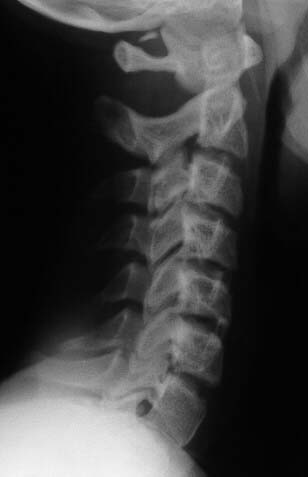

Adolescent. RTA knockdown. ATLS protocols. Put in hard collar. These films below obtained. no neck pain, no swelling, no neurology, no dysaethesia, no previous neck trauma. Closed # tibia.

Lateral

I cannot make a diagnosis from these films (which are clearly reproduced, I cannot decipher the information). There is a bony ossicle (?fx fragment) posteriorly between O-C1 and asymmetry of the atlas on open mouth odontoid. I would keep her neck braced and follow the clinical exam; probably with additional studies of the O-C1junction (CT +-MRI) and review with radiologist.

MRI was unremarkable except for showing the bony ossicle. Radiologists said the peg view was rotated.

Our radiologists tell me its part of a congenital arch. I have never seen this kind of remnant at this level. Has anyone else?